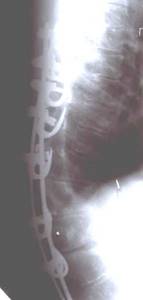

До сих пор в ортопедии принято множество методик измерения угла искривления позвоночника, и, соответственно, множество различных классификаций с разными величинами углов в градусах. Измеряется искривление так: на рентгенограмме надо провести несколько прямых линий между позвонками, а затем измерить углы между ними. В нашей стране наиболее распространена классификация, предложенная В.Д. Чаклиным. В иностранных научных источниках чаще приводится метод Дж. Кобба. Суть его заключается в следующем: на рентгеновском снимке позвоночника врач измеряет S-образное двойное искривление. В верхнем участке искривления с помощью линейки проводят две горизонтальные линии: одна над верхним позвонком, от которого идет кривизна, другая - над нижним. Если провести еще две линии, идущие перпендикулярно первым, образуется угол. Его и измеряют в градусах

Классификация выраженности сколиоза по В.Д. Чаклину (слева), по Лж. Коббу (справа) Степени тяжести сколиоза (углы искривления позвоночника, в градусах) Графический расчет на рентгенограмме: а - I степень; б - II степень; в - III степень; г - IV степень.

| По В.Д. Чаклину | По Дж. Коббу |

| I степень 180 - 175 | меньше 15 |

| II степень 175-155 | 20-40 |

| III степень 155-100 | 40-60 |

| IV степень меньше 100 | больше 60 |